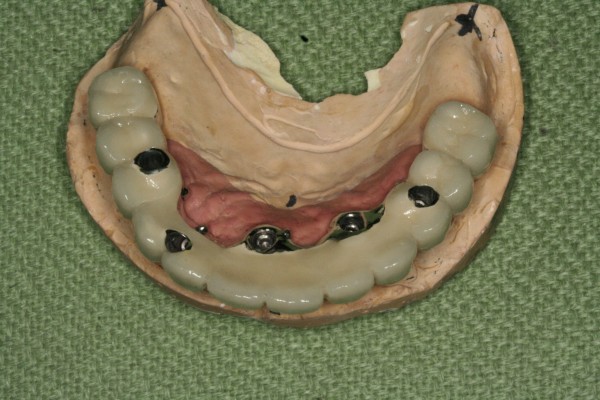

Milling bar 5 milling bar가 불편한 fixed implant bridge